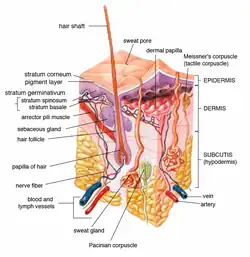

A poroma is a benign skin tumor derived from sweat glands. Although the original term poroma was initially used to describe a tumor derived from the ductal epithelium of eccrine sweat glands, the term is used in general reference to tumors derived from ductal portions of both eccrine and apocrine sweat glands. Specific subtypes are primarily defined by location of tumor, and include:[1][2]

An eccrine poroma specifically refers to a tumor derived specifically from the most apical portion of eccrine sweat gland (acrosyringium). They are most commonly found on acral distribution (on palms and soles), and most commonly in adults.[3][4]